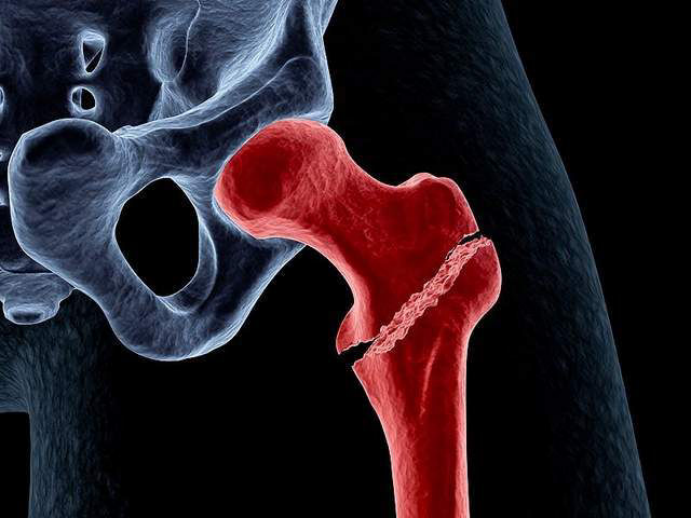

根据国外研究统计,老年人发生髋部骨折后,一年生存率只有约50%。因此,高龄老人发生此类骨折后,往往会被人们称为“人生最后一次骨折”。

蔡奶奶今年98岁高寿,因“跌伤致右髋部疼痛伴活动受限5天。”到我院骨伤科治疗。入院后,被诊断为“右侧股骨粗隆间骨折”。

“虽然骨折手术并不复杂,但是蔡奶奶属于超高龄患者,各器官功能退化,心、肺功能下降,尤其是对手术的承受力下降、麻醉耐受力的降低、术后感染、康复及一系列并发症,每一道都是难关。”副院长张有文详细介绍,如果保守治疗,蔡奶奶需长期卧床,也容易引发肺部感染、褥疮、深静脉血栓等一系列的并发症,严重可导致生命危险。